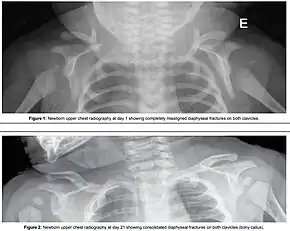

Typically the procedures are performed in the order listed and the sequence ends whenever a technique is successful.[11] Intentional fracturing of the clavicle, a procedure known as cleidotomy,[12][13] is another possibility at non-operative vaginal delivery prior to Zavanelli's maneuver or symphysiotomy, both of which are considered extraordinary treatment measures. Pushing on the fundus is not recommended.[1]

- Intentional causing clavicular fractures, which reduces the diameter of the shoulders that requires to pass through the birth canal;[2]